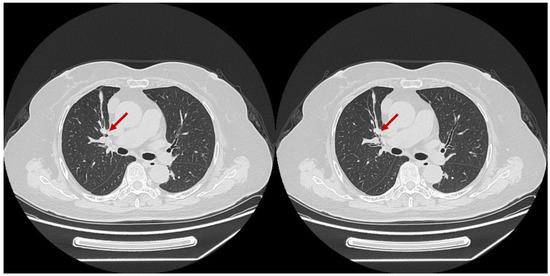

- Developments in low-dose CT screening;

- Artificial intelligence in lung cancer diagnosis;

- low-dose CT screening

- medical imaging

- lung nodules